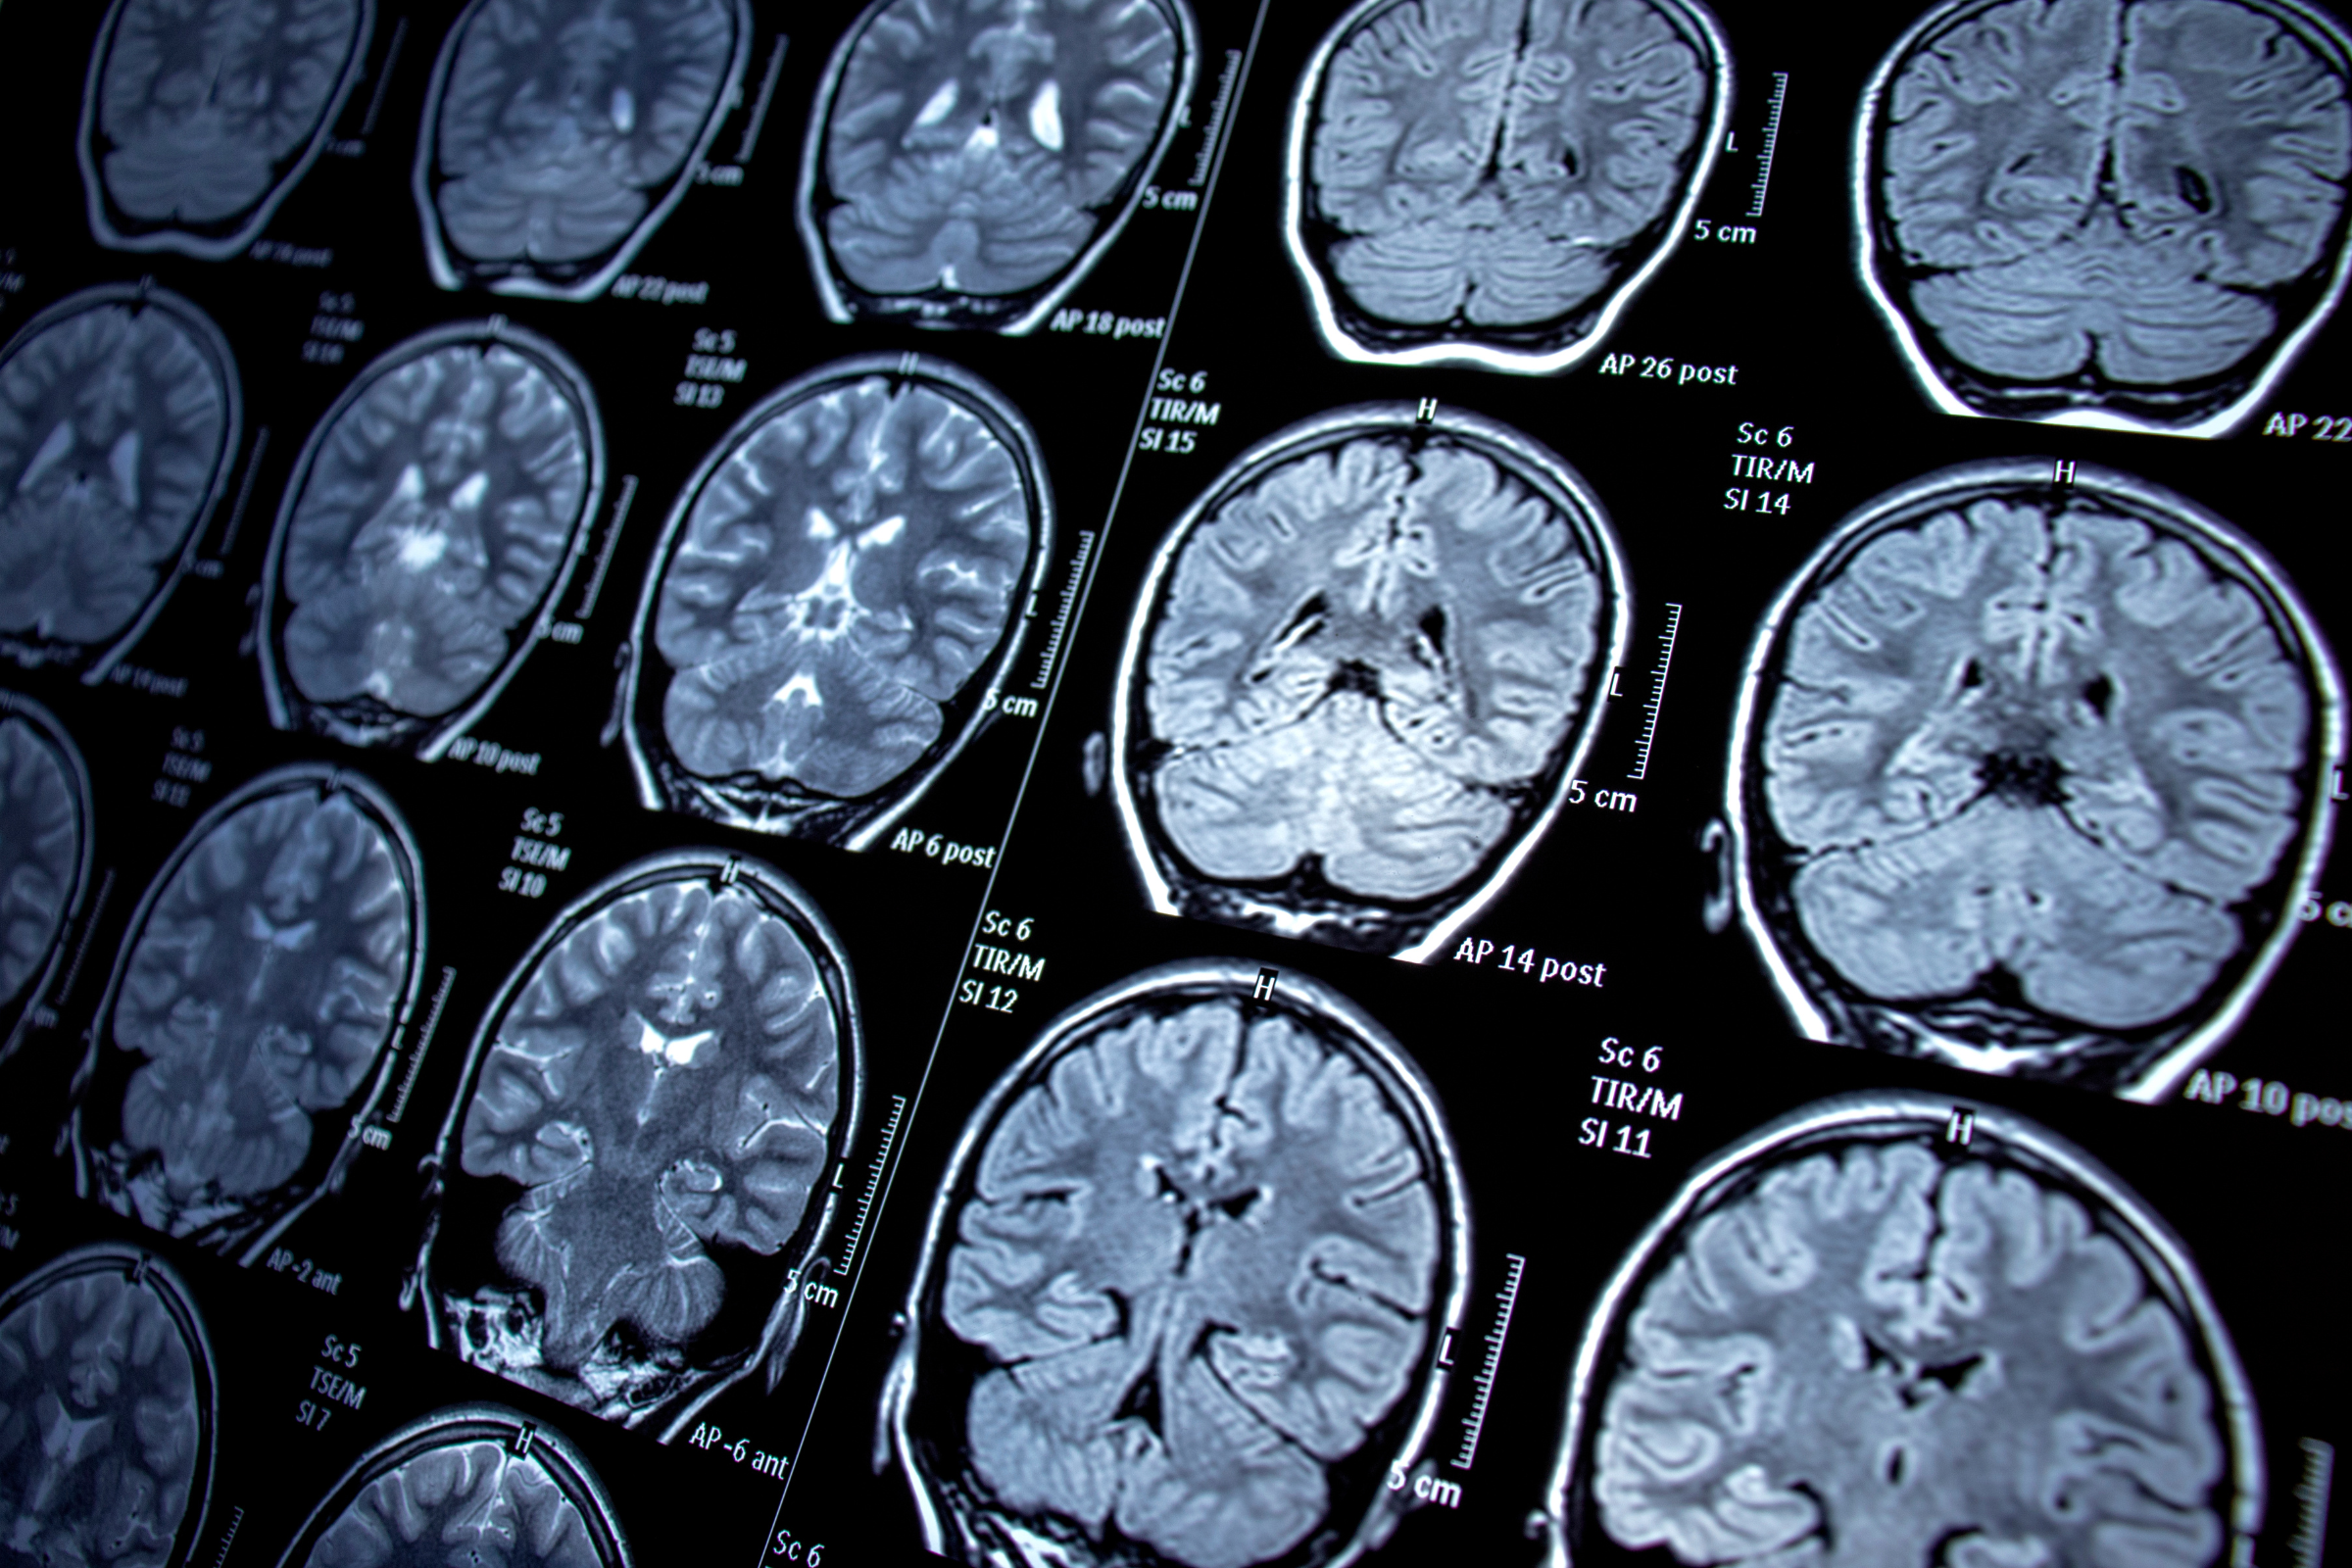

Medications can help control the seizures in some people, but around one-third of patients don’t respond to those drugs. The alternative is surgery, which is invasive and can cause damage to delicate brain tissue.

Neurona Therapeutics —a clinical stage biotherapeutics company— has developed a therapy called NRTX-1001, which consists of a specialized type of neuronal or brain cell derived from embryonic stem cells. These cells are injected into the brain in the area affected by the seizures where they release a neurotransmitter or chemical messenger that will block the signals in the brain causing the epileptic seizures.